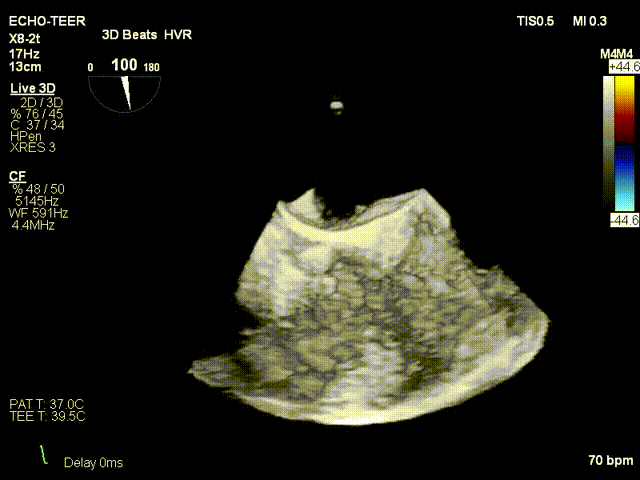

术前超声

术后超声